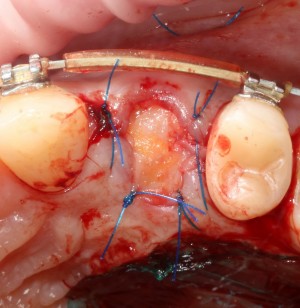

В этом случае мы используем Mucograft Seal как наименее травматичный и наиболее простой способ герметизации лунки:

Матрица подшивается узловыми швами к краям лунки, таким образом достигается ее герметичность:

И вот что важно про швы. Любые другие способы подшивания что матрицы, что десневого лоскута, например П-образные или Х-образные швы, во-первых, не обеспечивают нужной герметичности, а во вторых создают излишнее натяжение краев слизистой оболочки, что приводит их деградации и стимулирует атрофию тканей. Так что лучше потратить побольше времени и зашить лунку так, как надо, чем потом переживать за результат операции.